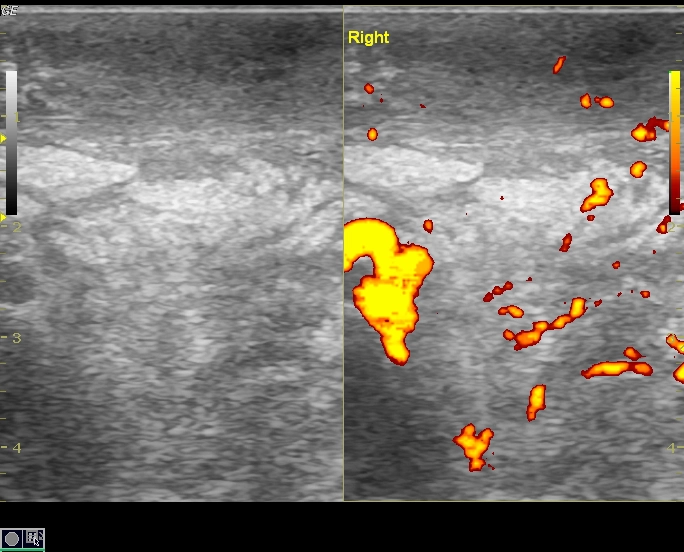

• Bìu và thừng tinh

• Bệnh lý viêm nhiễm

Viêm mô tế bào bìu (Scrotal cellulitis)

16/03/2026